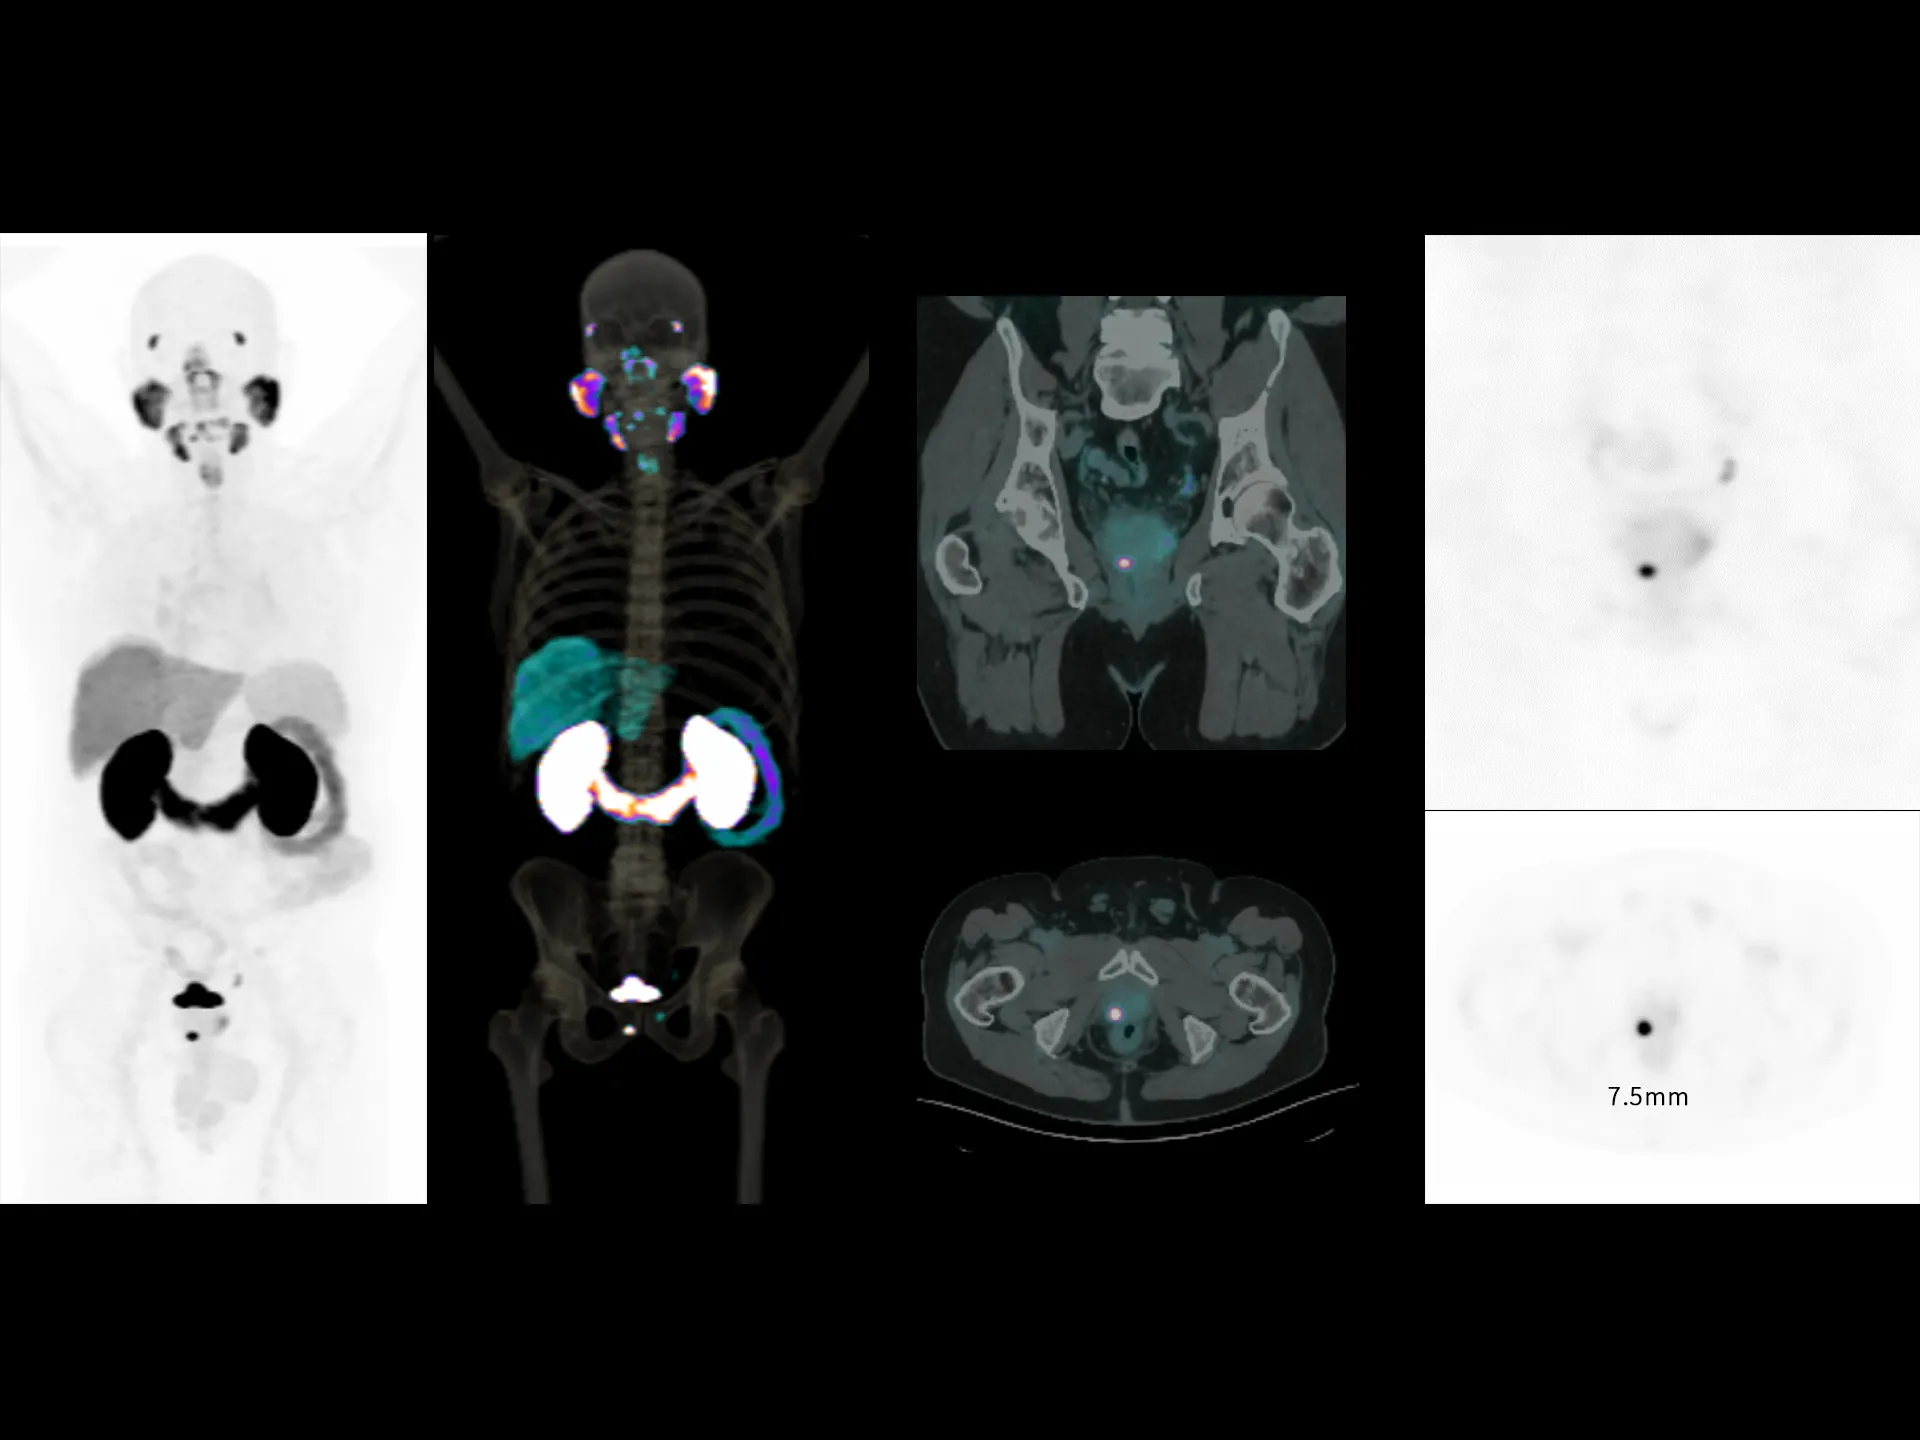

2.9 mm

Exceptional NEMA spatial resolution delivered by the finest crystal size of 2.76 mm in the industry.

Leading TOF resolution that boosts small lesion detectability and clarity.